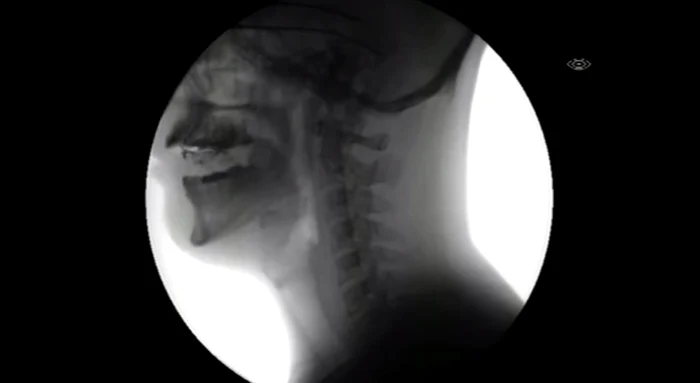

Video-ul fascinant urcat de utilizatorul Spladgum arată traseul pe care îl parcurg alimentele odată ingerate. În clip putem observa drumul mâncării și băuturii din gură, prin esofag și până în stomac. Și, în caz că erați curioși, puteți vedea și cum arată o inimă care bate.